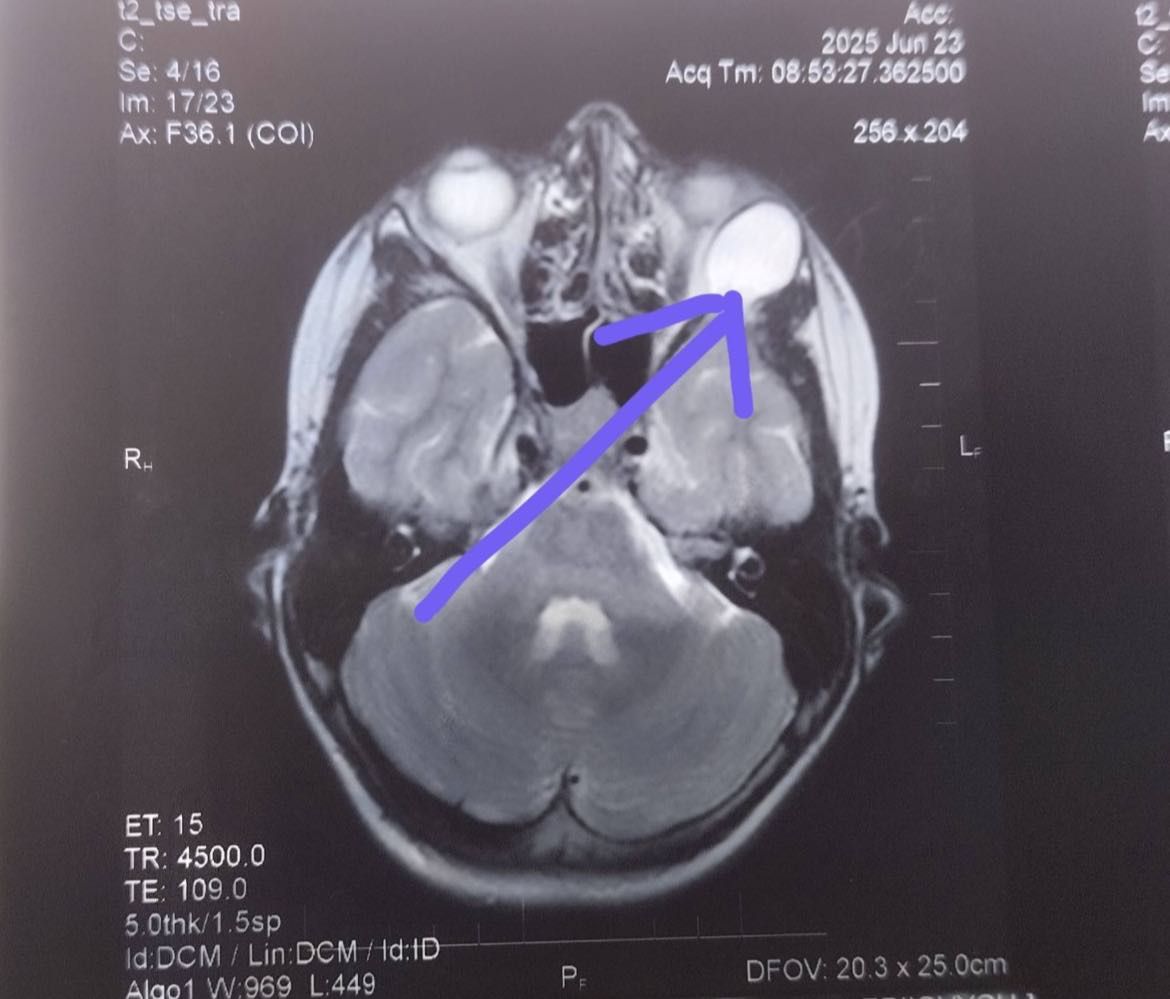

За інформацією лікарів, 14-річний пацієнт звернувся по медичну допомогу зі скаргами на випинання лівого ока, появу косоокості та двоїння предметів. Після обстеження та МРТ-діагностики у хлопчика виявили новоутвір очної ямки великих розмірів (приблизно 20 мм), який змістив очне яблуко з правильного положення.

«Пацієнту діагностували дермоїдну кісту. Фахівці спеціалізованого хірургічного відділення, лікарі-офтальмохірурги дитячі Наталія Мержиєвська та Віталій Піщук, провели складну операцію з видалення пухлини під загальним наркозом», – повідомили у лікарні.